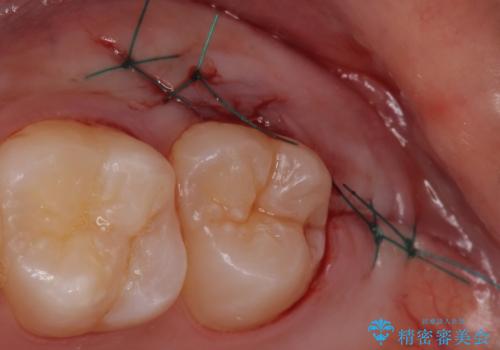

また術後丁寧に縫合をすることで治癒後の歯茎の状態もきれいにすることができます。

- 外科手術のため、術後に出血、痛みや腫れ、違和感を伴います